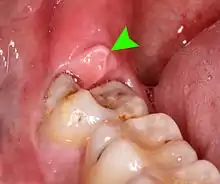

| Pericoronitis associated with the lower right third molar (wisdom tooth). | |

Pericoronitis is inflammation of the soft tissues surrounding the crown of a partially erupted tooth,[1] including the gingiva (gums) and the dental follicle.[2] The soft tissue covering a partially erupted tooth is known as an operculum, an area which can be difficult to access with normal oral hygiene methods. The hyponym operculitis technically refers to inflammation of the operculum alone.

Pericoronitis is caused by an accumulation of bacteria and debris beneath the operculum, or by mechanical trauma (e.g. biting the operculum with the opposing tooth).[3] Pericoronitis is often associated with partially erupted and impacted mandibular third molars (lower wisdom teeth),[4] often occurring at the age of wisdom tooth eruption (15-26).[5][6] Other common causes of similar pain from the third molar region are food impaction causing periodontal pain, pulpitis from dental caries (tooth decay), and acute myofascial pain in temporomandibular joint disorder.

- Tenderness, erythema (redness) and edema (swelling) of the tissues around the involved tooth,[9] which is usually partially erupted into the mouth. The operculum is characteristically very painful when pressure is applied.[2]

- Formation of pus,[9] which can be seen exuding from beneath the operculum (i.e. a pericoronal abscess), especially when pressure is applied to the operculum.[2]

- Signs of trauma on the operculum, such as indentations of the cusps of the upper teeth,[9] or ulceration.[4] Rarely, the soft tissue around the crown of the involved tooth may show a similar appearance to necrotizing ulcerative gingivitis.[11]